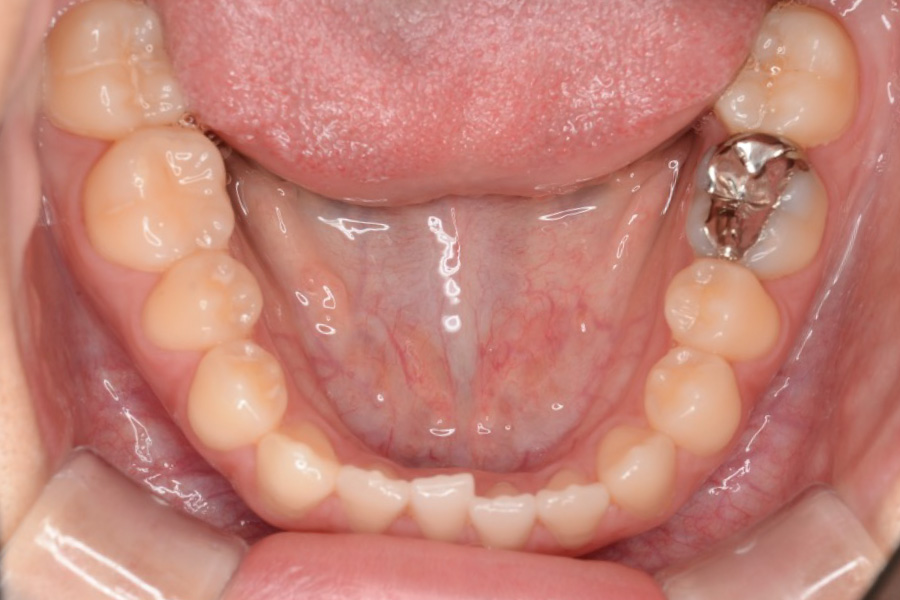

治療後

主訴 前歯で噛めない

治療内容 インビザライン矯正

非抜歯